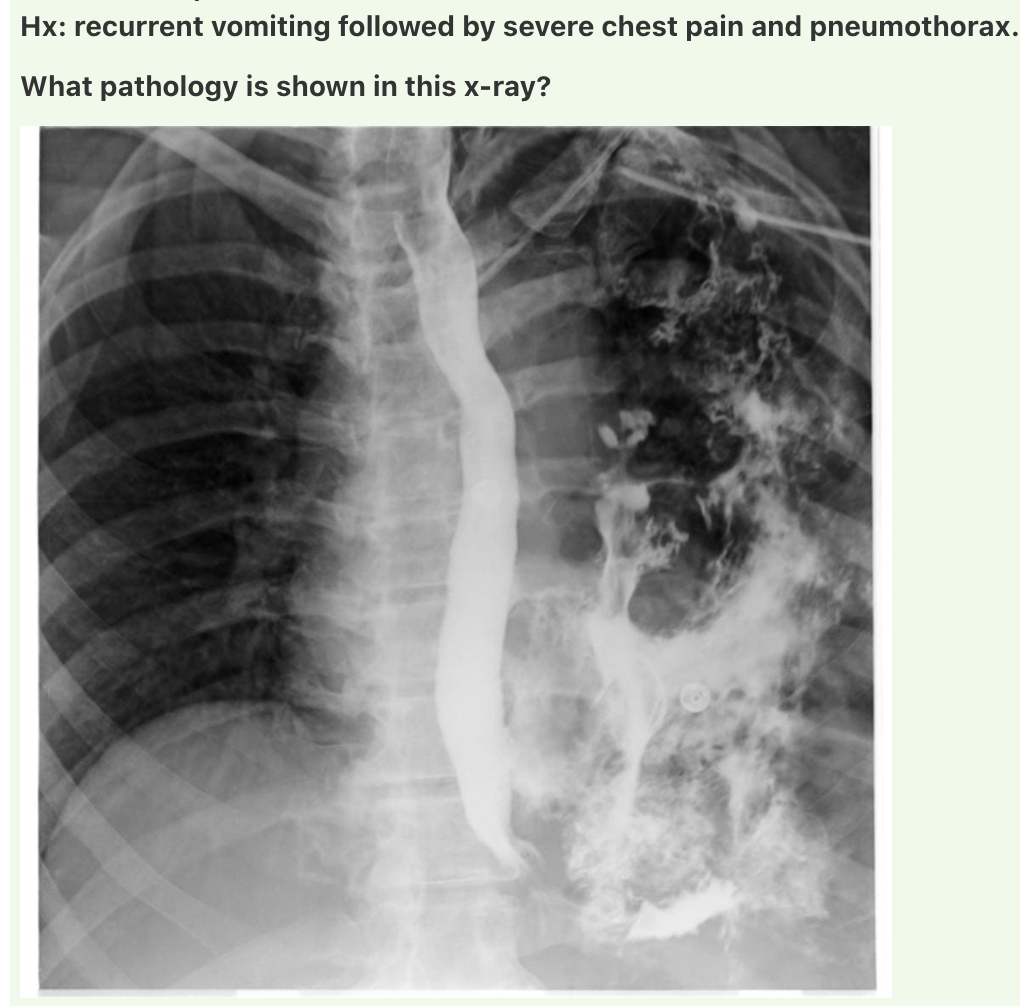

Answer: Boerhaave’s syndrome